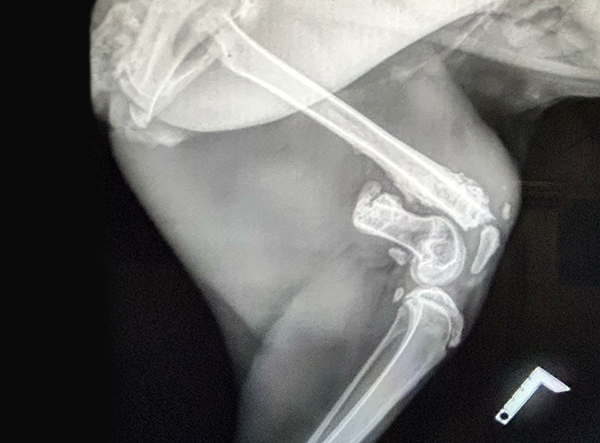

In April 2025, a stunning caracal suffering from a femur fracture began its road to recovery — and is now on its way to roaming freely in the wild.

The femur fracture was surgically treated by Dr. Matan Or, using a 3.5 LeiLOX Locking Bridge Plate to provide stable fixation and support the healing process. The LeiLOX system is designed to offer reliable stability while minimizing soft tissue disruption, which is crucial for optimal recovery and a safe return to natural mobility. Its locking mechanism ensures strong fixation, and the bridging technique helps maintain blood supply to the bone, supporting natural bone regeneration.